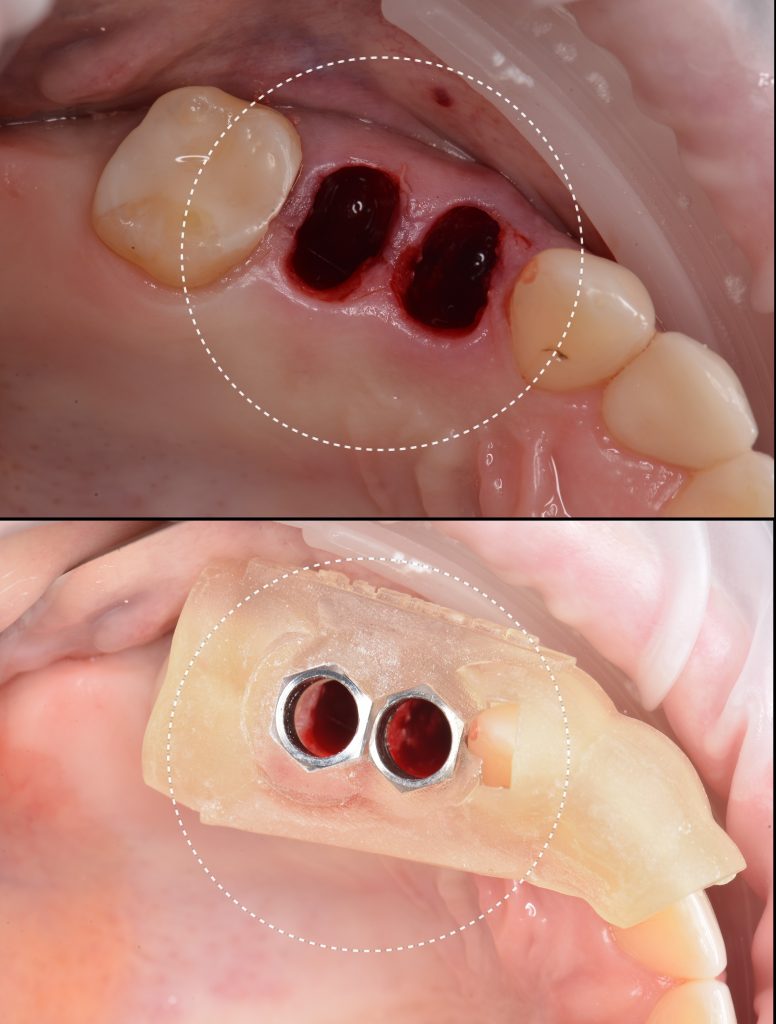

A template for guided implant surgery was planned and manufactured based on these digital models for the replacement of teeth 24 (Universal 12) and 25 (Universal 13)

Based on digital models, a virtual design of a template has been planned for the replacement of tooth 36 (Universal 19)

The result of collaboration with Diagnocat AI is a favorable outcome of the orthodontic and surgical stages of treatment